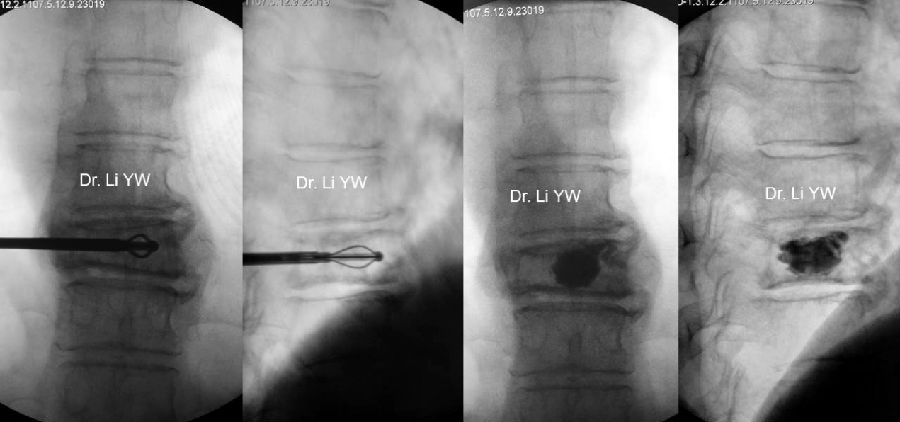

(六)开展网袋技术治疗脊柱转移癌

(十)省内首家、国内第四家开展PVP技术

率先将PVP术应用到颈2椎体水平,并陆续开展PKP、经皮网袋骨水泥技术、单侧穿刺弯角注入器双侧注入骨水泥等微创技术。

(十一)可弯曲性骨水泥注入器治疗骨质疏松性椎体骨折技术

球囊多点撑开结合过伸体位治疗椎体骨折技术。

可弯曲性骨水泥注入器治疗骨质疏松性椎体骨折技术,发表在《中华放射学杂志》。

球囊多点撑开结合过伸体位治疗椎体骨折技术,发表在《中国全科医学》。